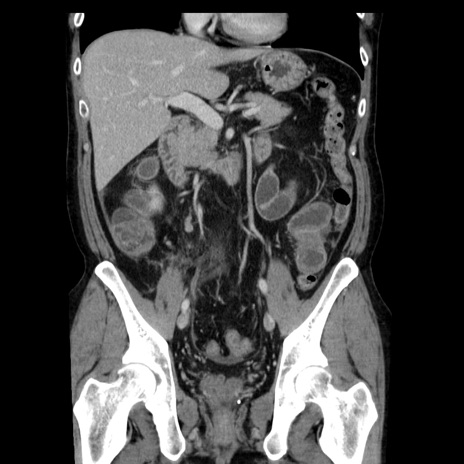

症例29(冠状断像)

【症例】40歳代男性

【現病歴】2日前から胃痛あり。徐々に周期的な激痛に変化した。本日になっても激痛があるため受診。

【身体所見】意識清明、BT 38-39℃台あり、腹部:膨満、やや硬、右下腹部に圧痛あり。

【データ】WBC 8500、CRP 23.26